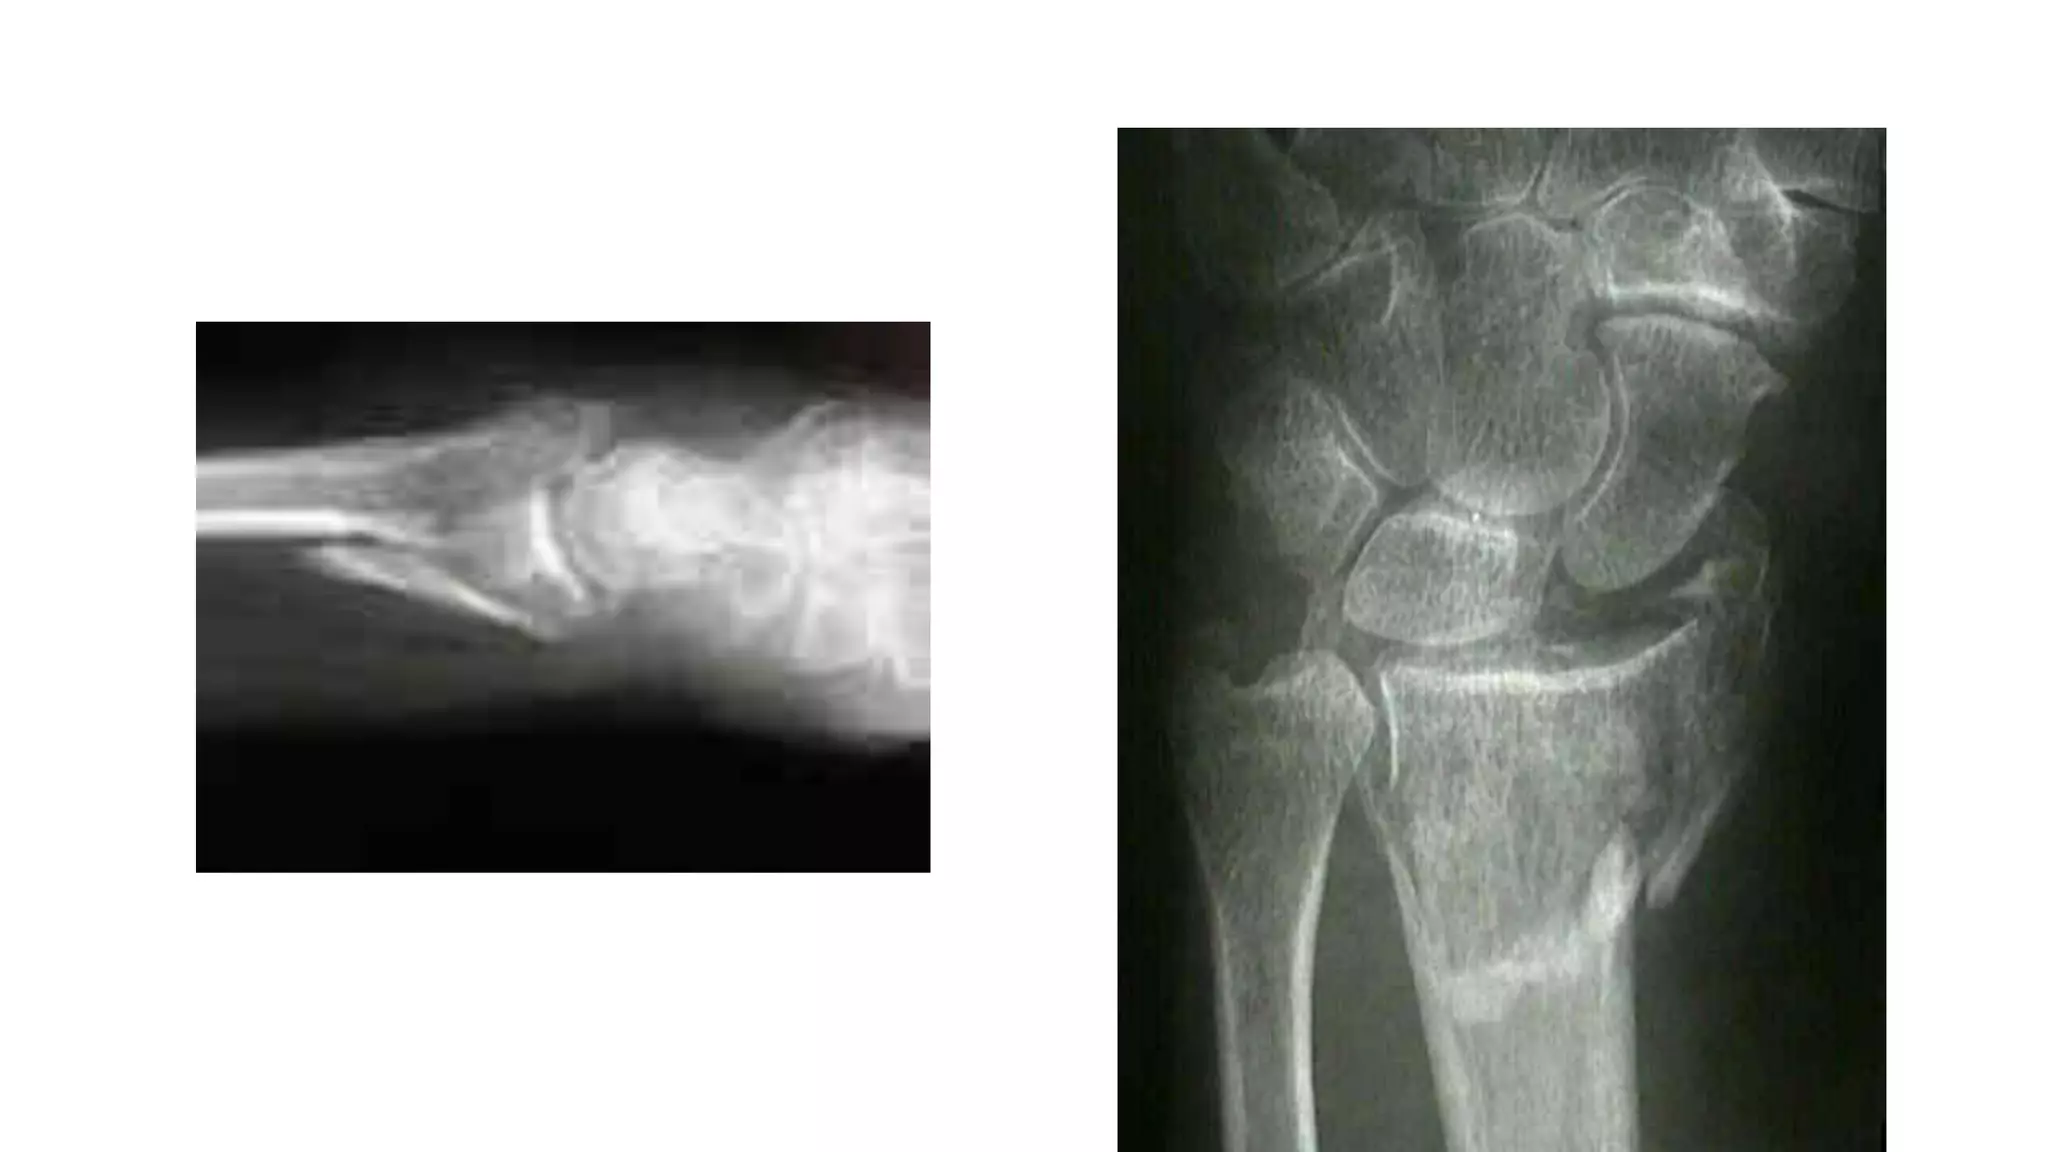

Volar and Dorsal Barton fractures — OrthopaedicPrinciples.com

Barton’s fracture

Bartons fracture ,What to know?